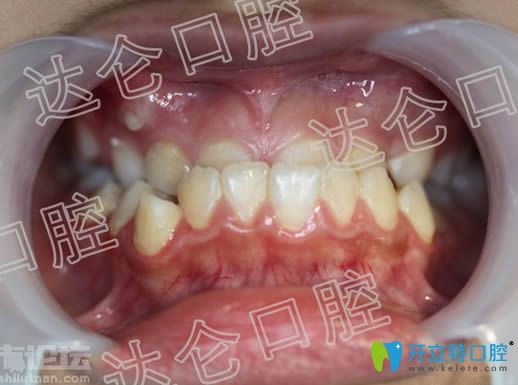

【地包天矯正術(shù)前照】:

【矯正前的近照】: